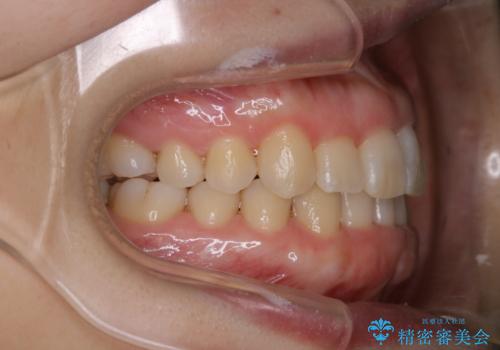

インビザライン・ライトでの抜歯矯正治療 (スリーインサイザー仕上げ)

- 上下の前歯のがたつきが気になるとのことで来院されました。最短治療とインビザラインでの矯正治療をご希望されました。

前歯のがたつきを無くすためには、スペースを確保する必要があります。上の前歯のがたつきは軽度ながたつきのため、歯と歯の間を研磨をして、そのスペースを使い並べていきます。下の前歯は、1本前歯を抜いて研磨せずに、その抜歯したスペースを使い並べることになりました。

インビザライン・ライトにて矯正治療を行うことになりました。

下の前歯は、スリーインサイザー仕上げと言って、通常前歯は4本ありますが(犬歯はいれていない)、そのどれか1本を抜歯して前歯を3本にして矯正治療を行うことを言います。また、先天的に歯の本数が少ない方もいますので、矯正治療を行っていなくても元々スリーインサイザーの方もいます。

インビザラインでの矯正治療の場合、装着時間や交換のタイミングは自己管理のため、患者さん自身にも頑張ってもらう必要があります。